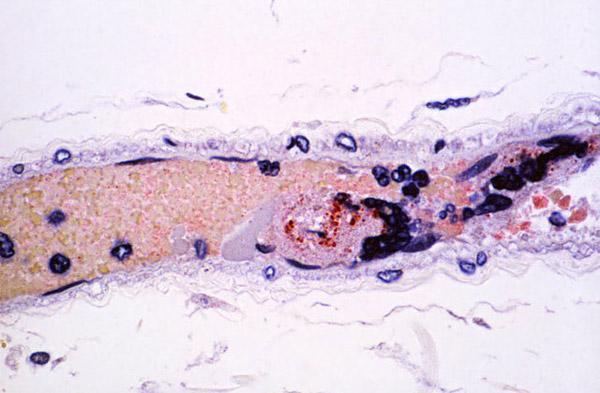

Mikroba karşı erken tedavi hastalardaki ateşi ve hastalığın şiddetini kısmen azaltıyor ancak ölümleri engelleyemiyor.

Nipah virüsü ateş, baş ağrısı, boğaz ağrısı ve kaslarda ağrı gibi belirtilerle kendini gösteriyor, gribe benziyor.

Ancak Nipah virüsü bulaşmış bazı insanlarda belirtiler hemen ortaya çıkmıyor.

İlerleyen safhada ise belirtiler baş dönmesi, yorgunluk, bilinç değişikliklerine dönüşebiliyor.